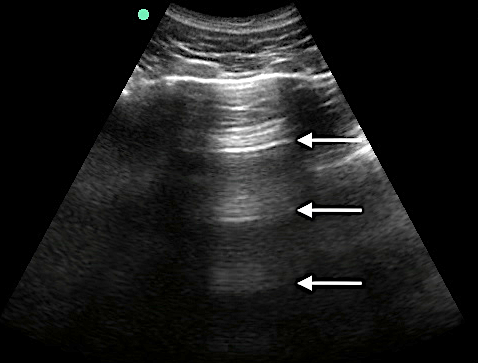

- Figure 4. A-lines

Video 1. A-lines - Occur from the emitted US wave reflecting back and forth between the transducer and the pleural line

- The distance from transducer to pleural line is the same as between the equidistant intervals separating each subsequent A-line.

- The artifacts’ brightness decreases with depth as energy is lost through repeated reflections.